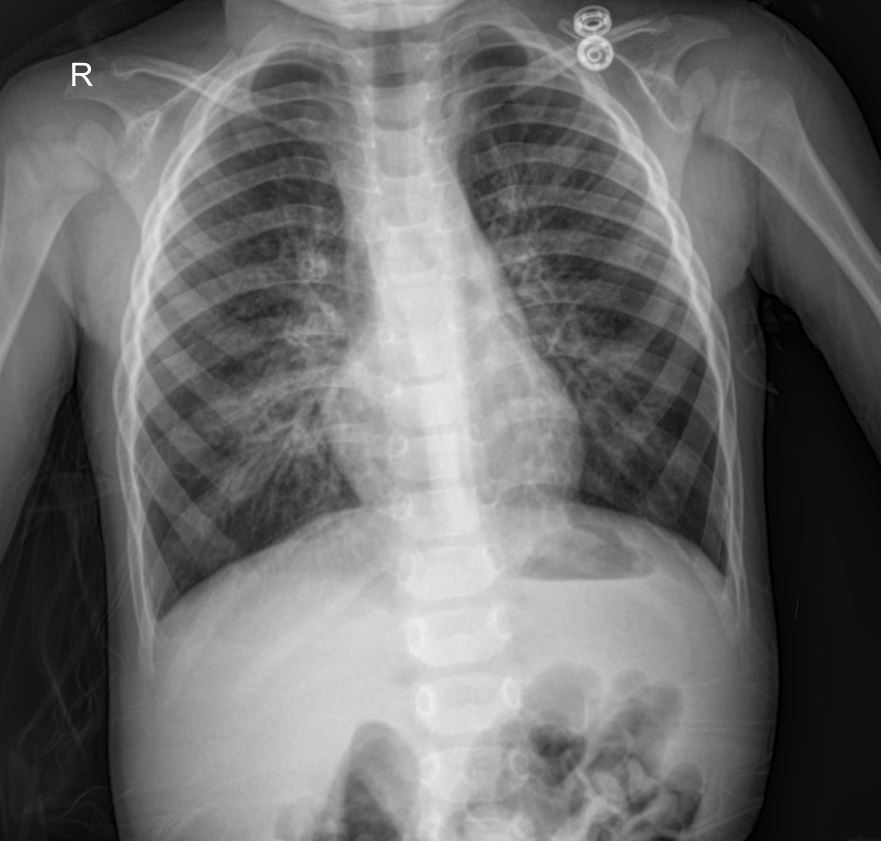

The initial chest X-ray revealed significant infiltrates in the right upper lobe, consistent with a consolidative process. The findings raised suspicion for a bacterial pneumonia, but given the lack of response to broad-spectrum antibiotics and the clinical context, other possibilities, including tuberculosis, were strongly considered. The “R” marker indicates the right side of the patient. The presence of these localized, dense infiltrates in a young patient with prolonged symptoms is a key finding that guided further diagnostic workup.

This case highlights the importance of considering atypical presentations and alternative diagnoses when initial treatments fail. The persistent right upper lobe infiltrates on the chest X-ray, coupled with an inadequate response to standard antibiotics for bacterial pneumonia, raised a high index of suspicion for tuberculosis. The subsequent positive AFB smear in the sputum confirmed the diagnosis, allowing for targeted anti-tuberculosis therapy. Early initiation of appropriate anti-tuberculosis medication is critical for effective treatment and preventing further transmission. The patient’s history of a vancomycin reaction also underscores the need for careful medication selection and monitoring.